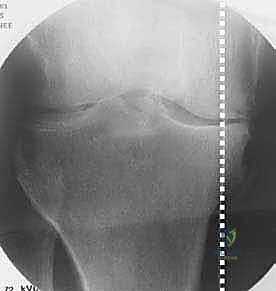

في الحالة الطبيعية الميكانيكية، يمر "محور تحمل الوزن" (Weight-bearing axis) مباشرة عبر منتصف الركبة، مما يوزع الضغط بالتساوي. ولكن، عند حدوث تقوس في الساقين (Varus Deformity)، ينزاح هذا المحور إلى الداخل، مما يضع ضغطاً هائلاً ومدمراً على الغضروف الداخلي للركبة.

هذا الضغط المستمر يؤدي إلى تآكل الغضروف بشكل أسرع من الطبيعي، مما يسبب احتكاك العظم بالعظم، وهو ما يُعرف بخشونة الركبة. هنا يأتي دور الجراحة لإعادة توجيه هذا المحور نحو الجزء الخارجي السليم من الركبة.

تُعد الأشعة السينية (X-rays) الممتدة من الحوض إلى الكاحل (Scanogram) ضرورية جداً لحساب زاوية التقوس بدقة وتحديد مقدار التعديل المطلوب جراحياً.

قبل العملية، يتم قياس زوايا الركبة بدقة متناهية. كل درجة من درجات التعديل يتم حسابها مسبقاً.

استخدام التخطيط الرقمي يضمن عدم حدوث تصحيح مفرط (Over-correction) أو تصحيح ناقص (Under-correction)، وهو ما يميز الجراح الخبير عن غيره.